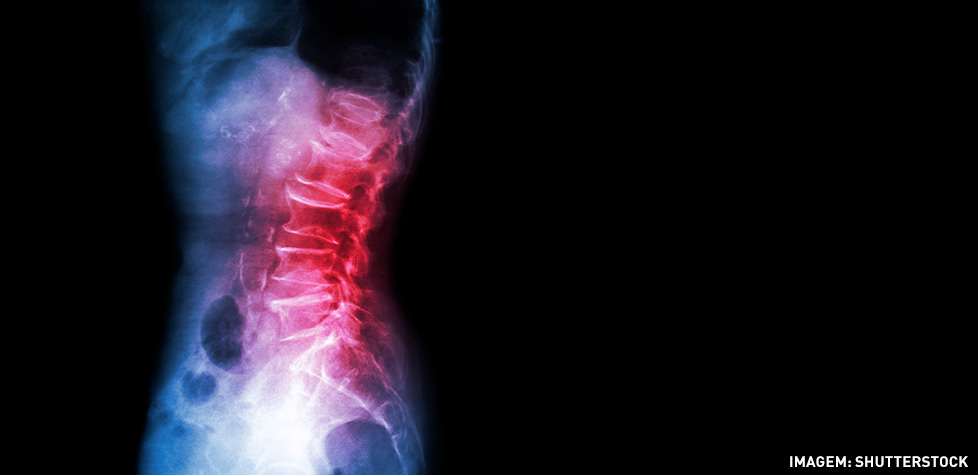

O bico de papagaio é o nome popular de um problema conhecido como osteofitose e são lesões que se apresentam na coluna vertebral, gerando os chamados osteófitos que, por sua vez, são como um prolongamento dos ossos, que aparecem por conta da progressão do problema. Isso ocorre graças à deposição de cálcio, mineral que compõe os ossos, na região.

São lesões progressivas, ou seja, que não surgem do dia para a noite. Elas são o resultado de anos de deposição de cálcio nos ossos, até que a pontinha se forme e fique visível nos exames de raio-x.

O diagnóstico, portanto, é feito com um exame bem simples: o raio-x. As imagens são bem claras e é possível ver perfeitamente a formação do osteófito ao bater o olho no resultado.